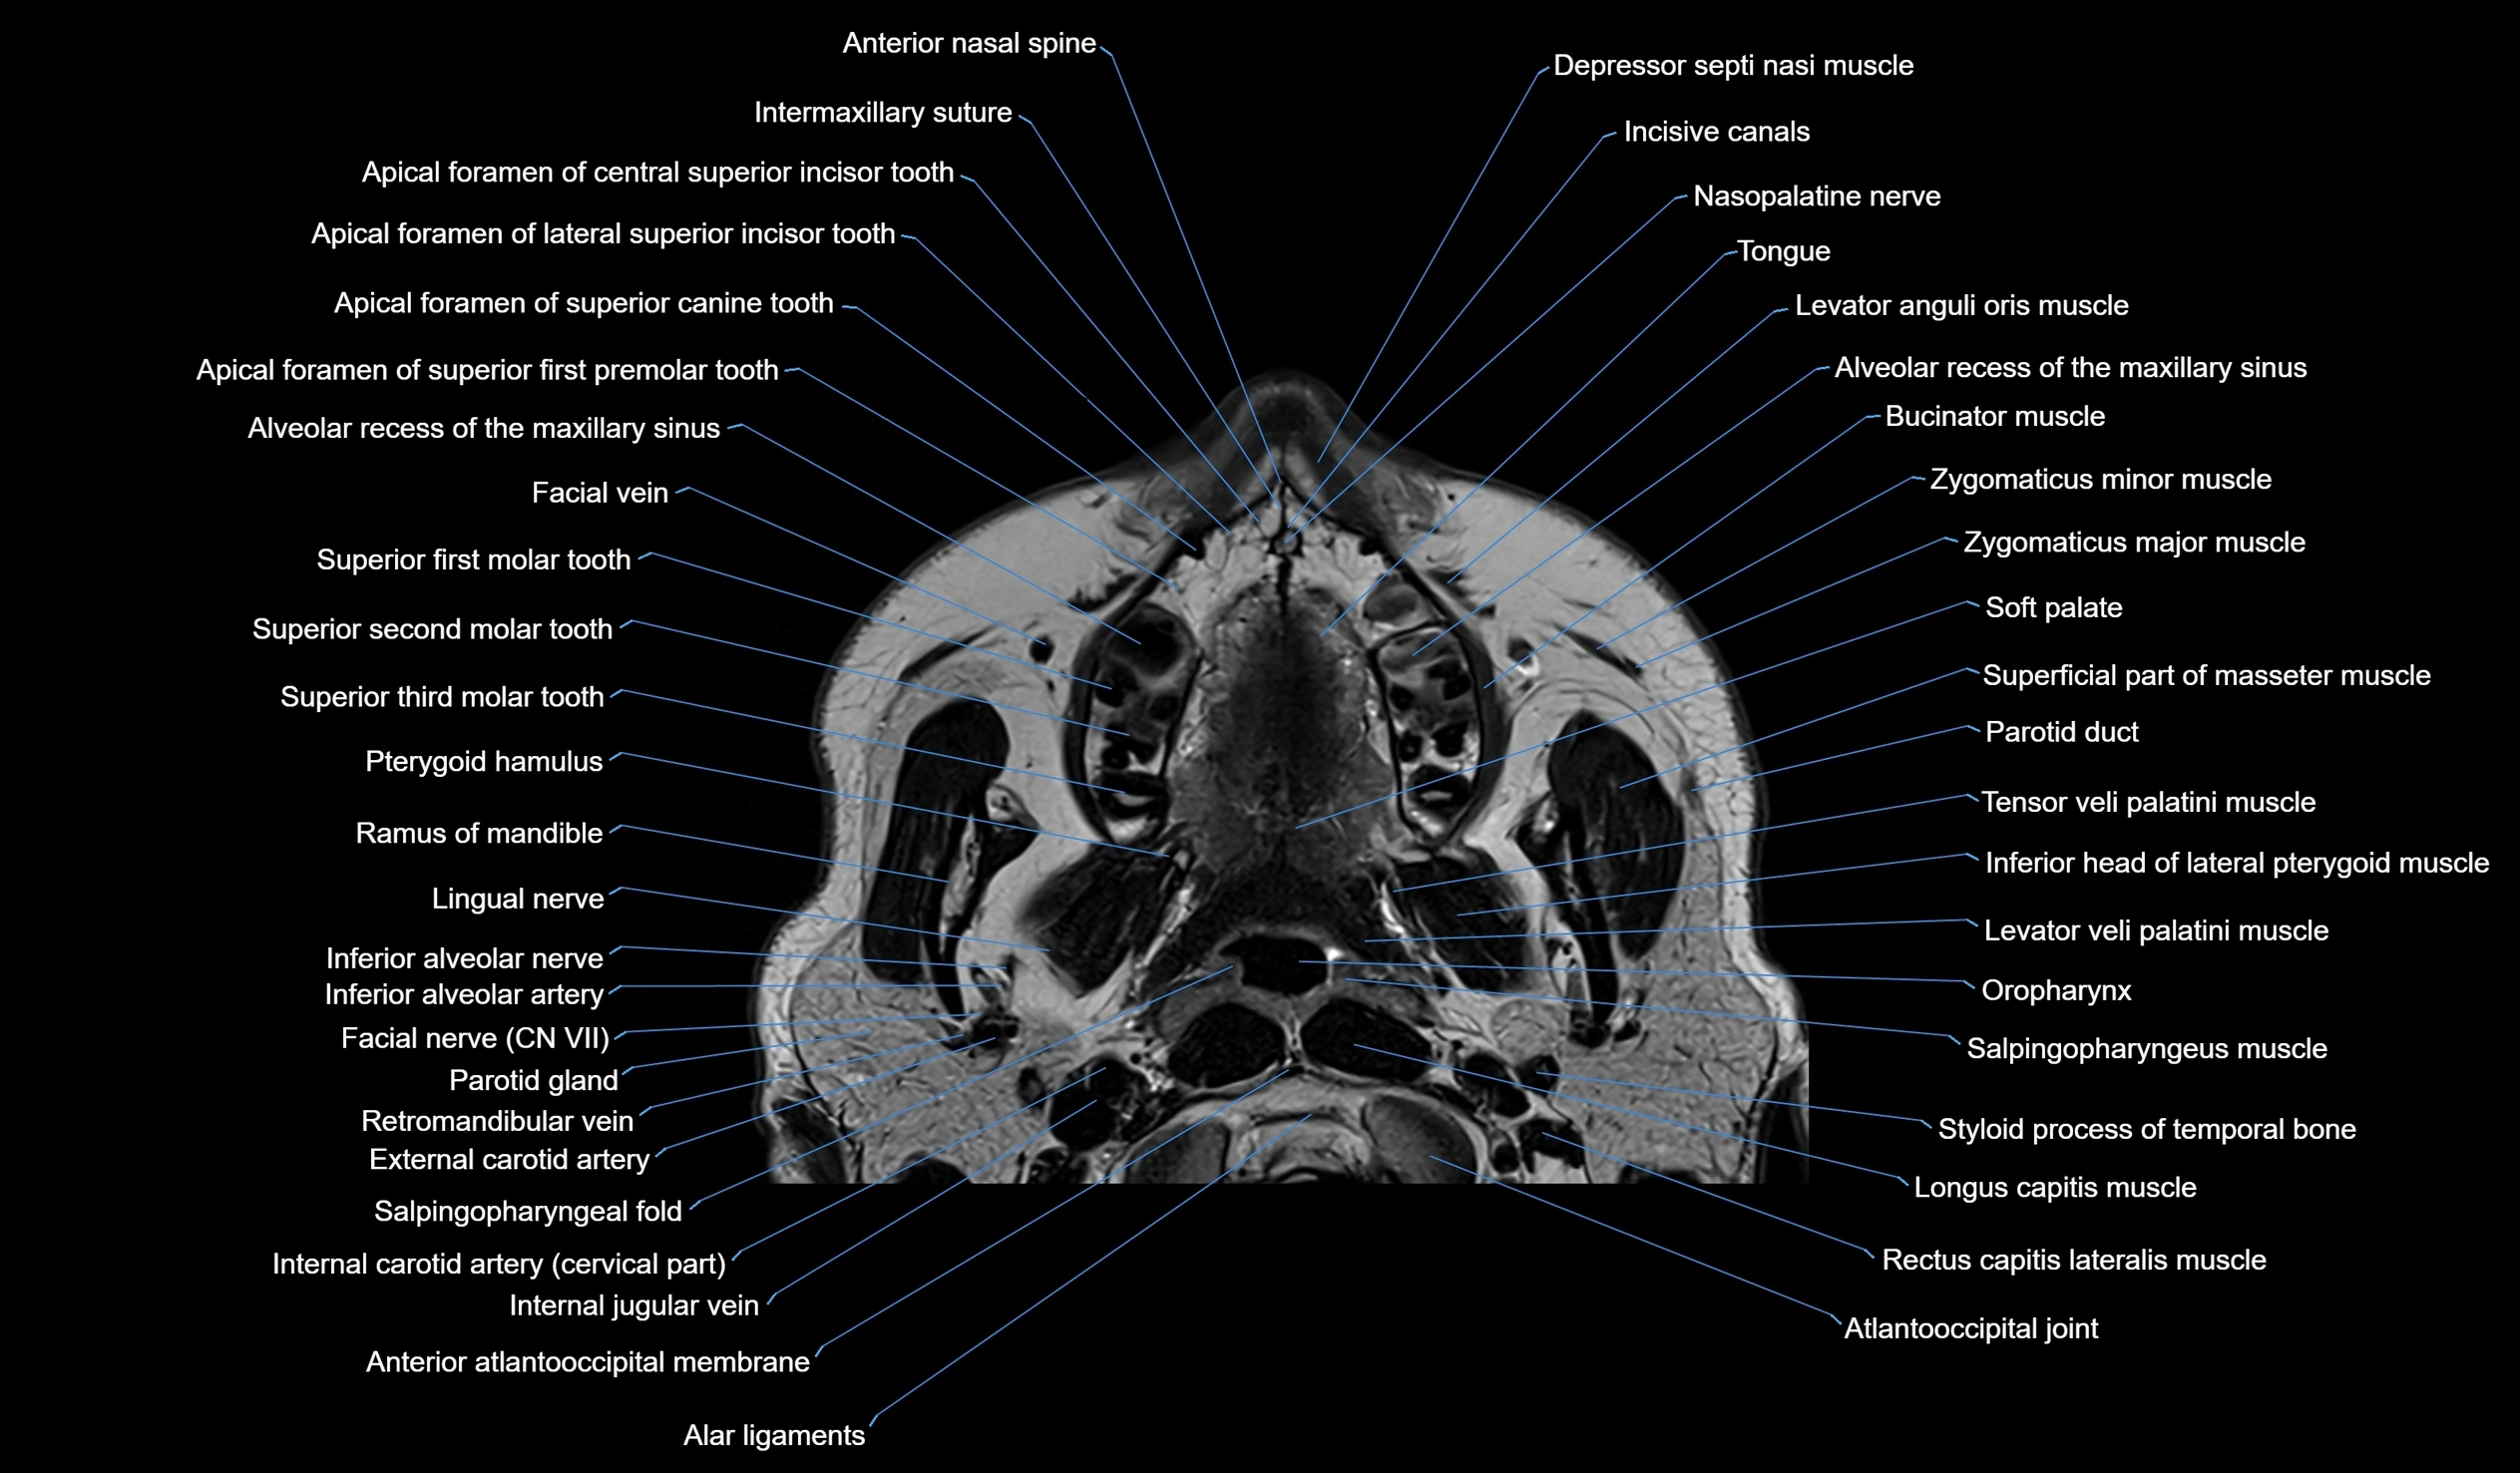

MRI images